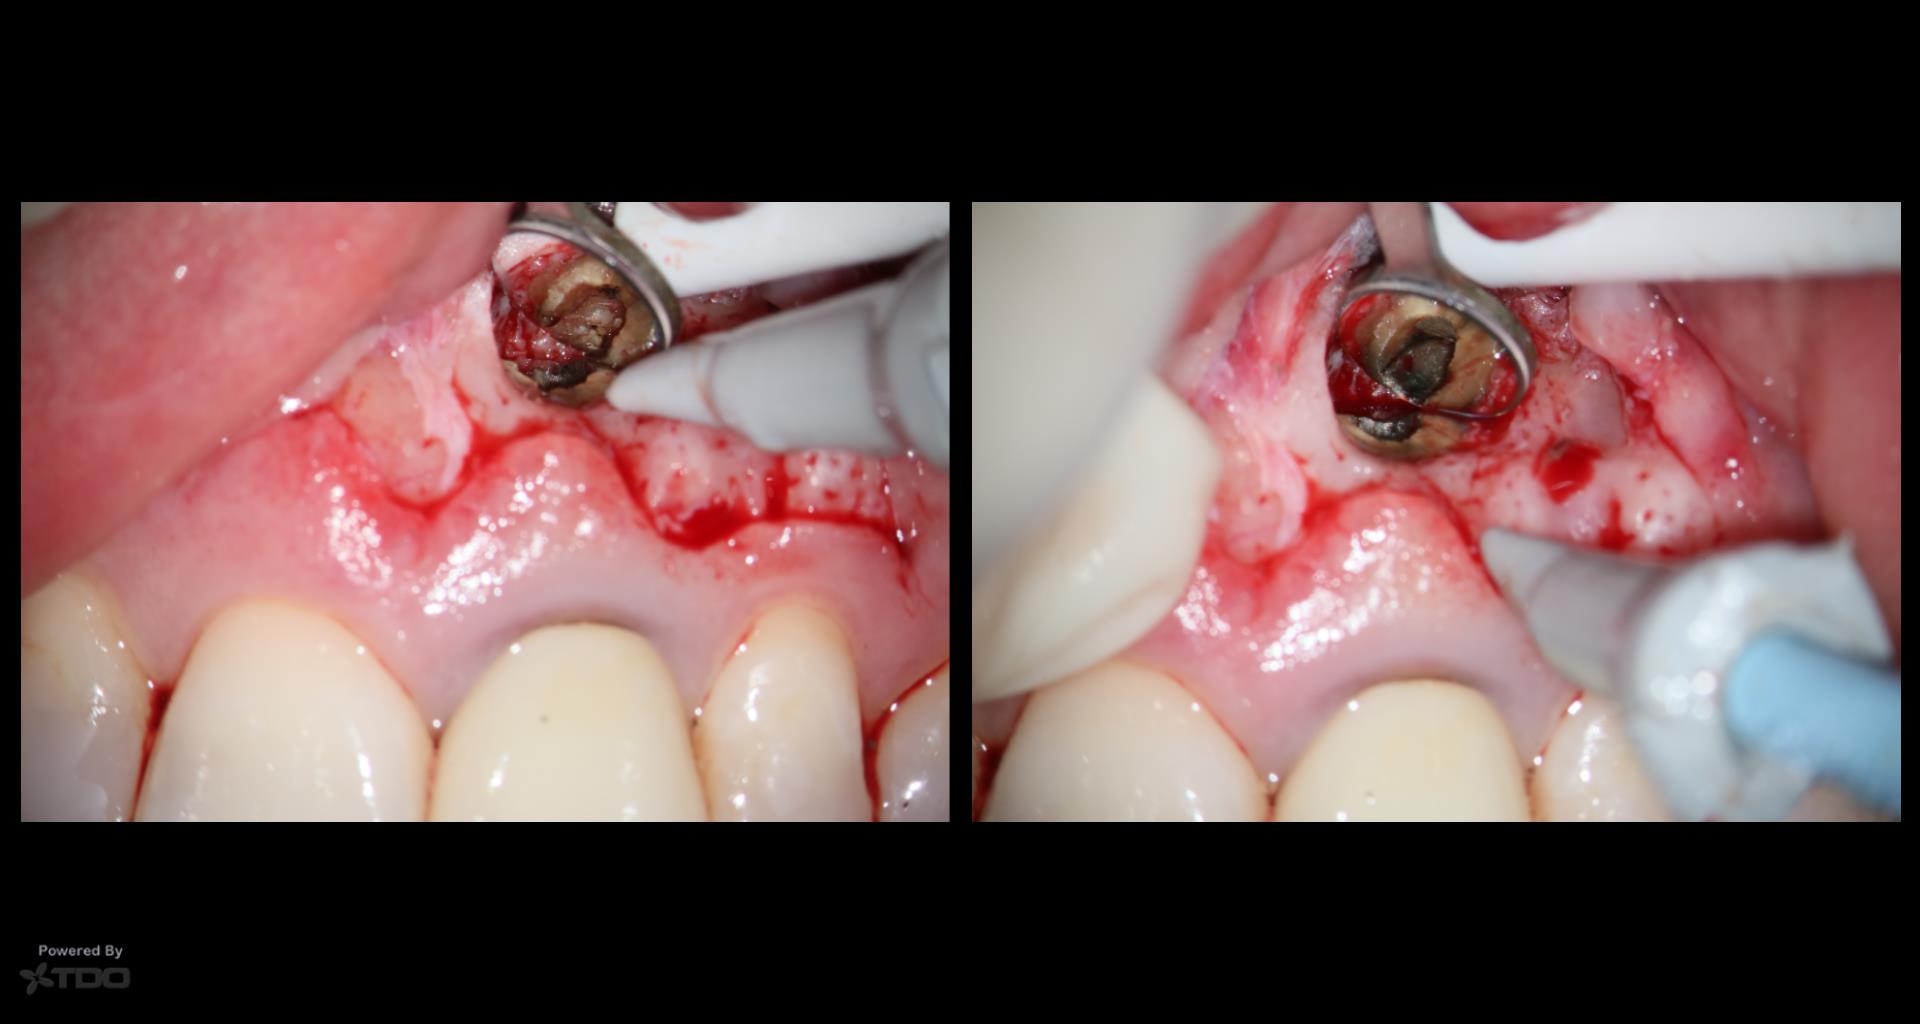

This was interesting because a root frac ture was seen where the prior apico was done. The MTAS was removed and Brassler putty used in this case. Will take a 1 yr CBCT and we will know more. Don’t usually get so much scar formation–so this was surprising…..